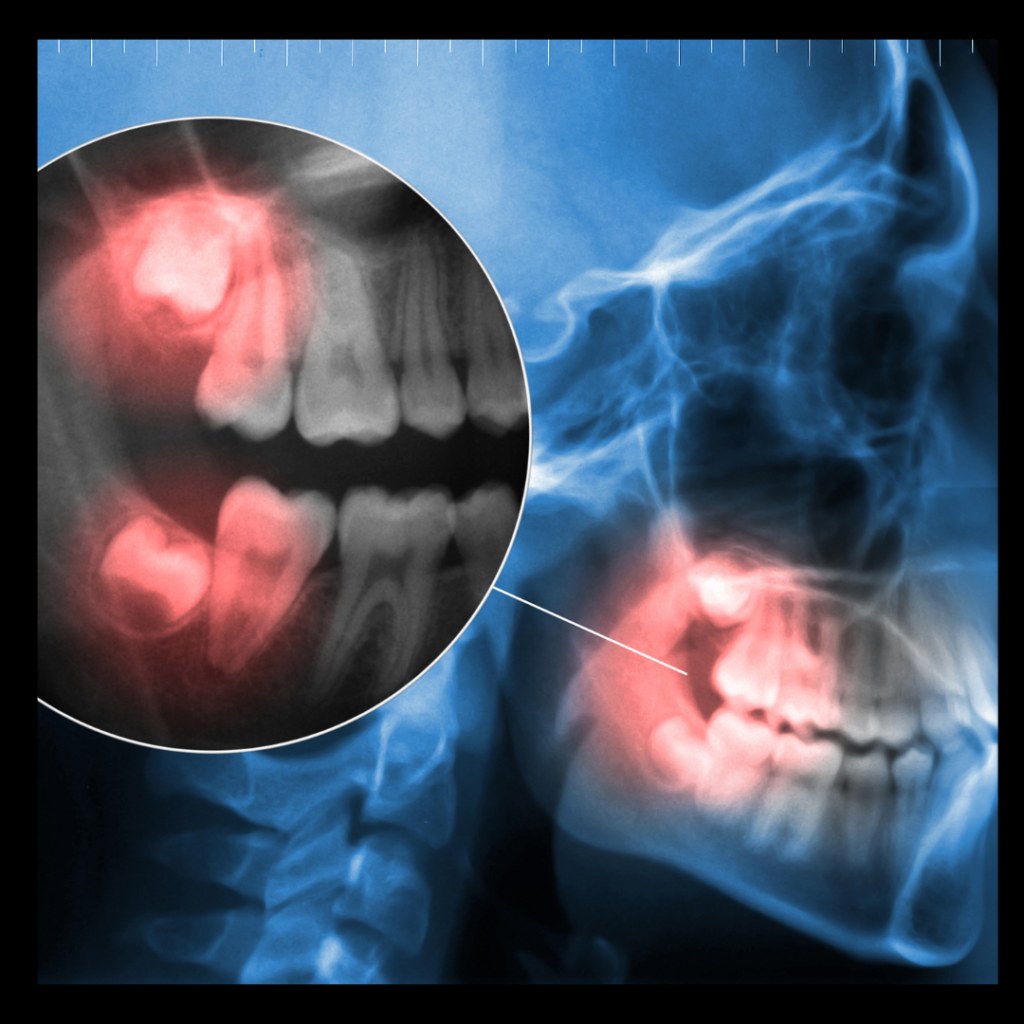

Impacted wisdom teeth are those that don’t fully erupt through the gums due to lack of space or improper alignment. They may remain trapped beneath the gum line or grow at an angle, pressing against neighboring teeth. Impaction can lead to:

Your dentist or oral surgeon will evaluate your wisdom teeth using X-rays to determine whether removal is necessary. Regular dental checkups are essential for monitoring the development of your wisdom teeth and catching potential issues early.

- Consultation and Evaluation: Your dentist will take X-rays to assess the position and condition of your wisdom teeth.